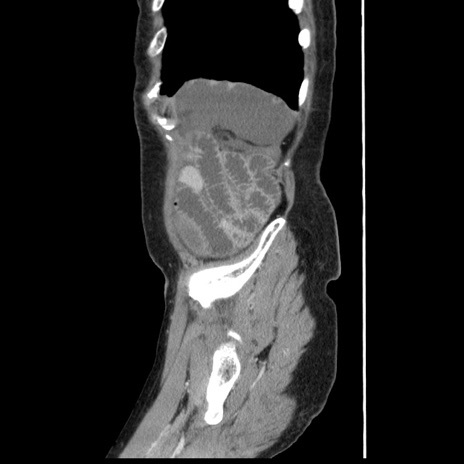

横断像

【症例】80歳代女性

【主訴】腹痛

【現病歴】8時間前から腹痛あり来院。

【既往歴】糖尿病、脂質異常症、子宮体癌にて子宮全摘術

【身体所見】意識清明・会話良好だが腹痛で苦悶様、全腹部にわたって反跳痛と圧痛あり

【データ】WBC 13600、CRP 0.14、LDH 224、CK 90